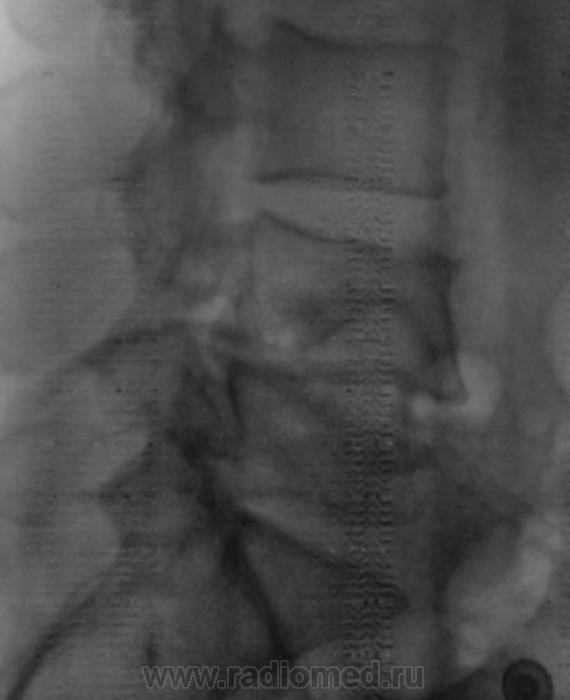

Ни анамнеза, ни возраста... Компрессионный перелом L4 и L5, вероятно, патологический.

Ни анамнеза, ни возраста...

Около 40 лет.

В анамнезе травма поясничной области.

Я то же за компрессионный перелом в L4 L5 + сколиотическое искривление в посничном отделе.